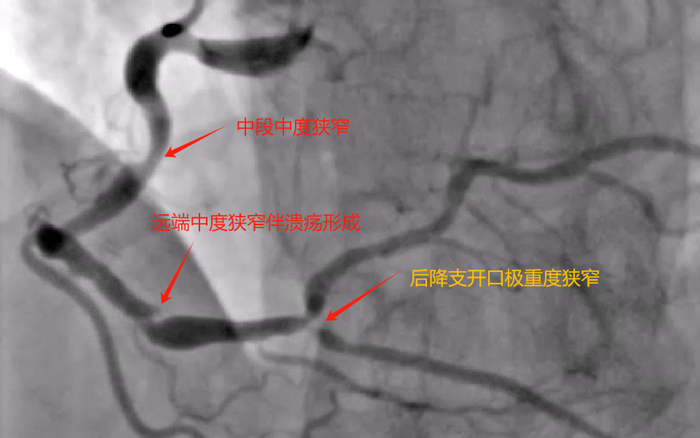

造影可见:左冠双开口,前降支近端及回旋支近端均重度狭窄;右冠极度扭曲,中段中度狭窄,远端中度狭窄伴溃疡形成,后三叉处及后降支极重度狭窄。造影结果比我预想的结果要差,多支血管病变,而且右冠病变很复杂。